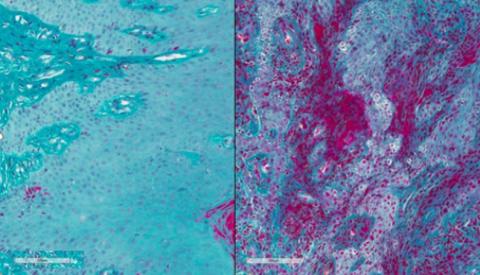

La parodontite est une infection bactérienne des tissus soutenant les dents. À ses débuts, la maladie parodontale provoque une rougeur et un gonflement (inflammation) des gencives (visuel de droite). Dans les stades plus avancés, l'os sous-jacent est endommagé, ce qui entraîne la perte des dents. La parodontite est due en partie à une réponse cellulaire immunitaire exagérée mais ses mécanismes moléculaires sous-jacents ne sont pas bien compris. « Une maladie parodontale grave peut entraîner la perte des dents et réduire considérablement la qualité de vie de nombreuses personnes, en particulier plus âgées ou qui n’ont pas accès aux soins dentaires », explique le Dr Rena D'Souza, Directrice du NIDCR.

À ses débuts, la maladie parodontale provoque une rougeur et un gonflement (inflammation) des gencives (visuel de droite) (Visuel Lakmali Silva, NIDCR)